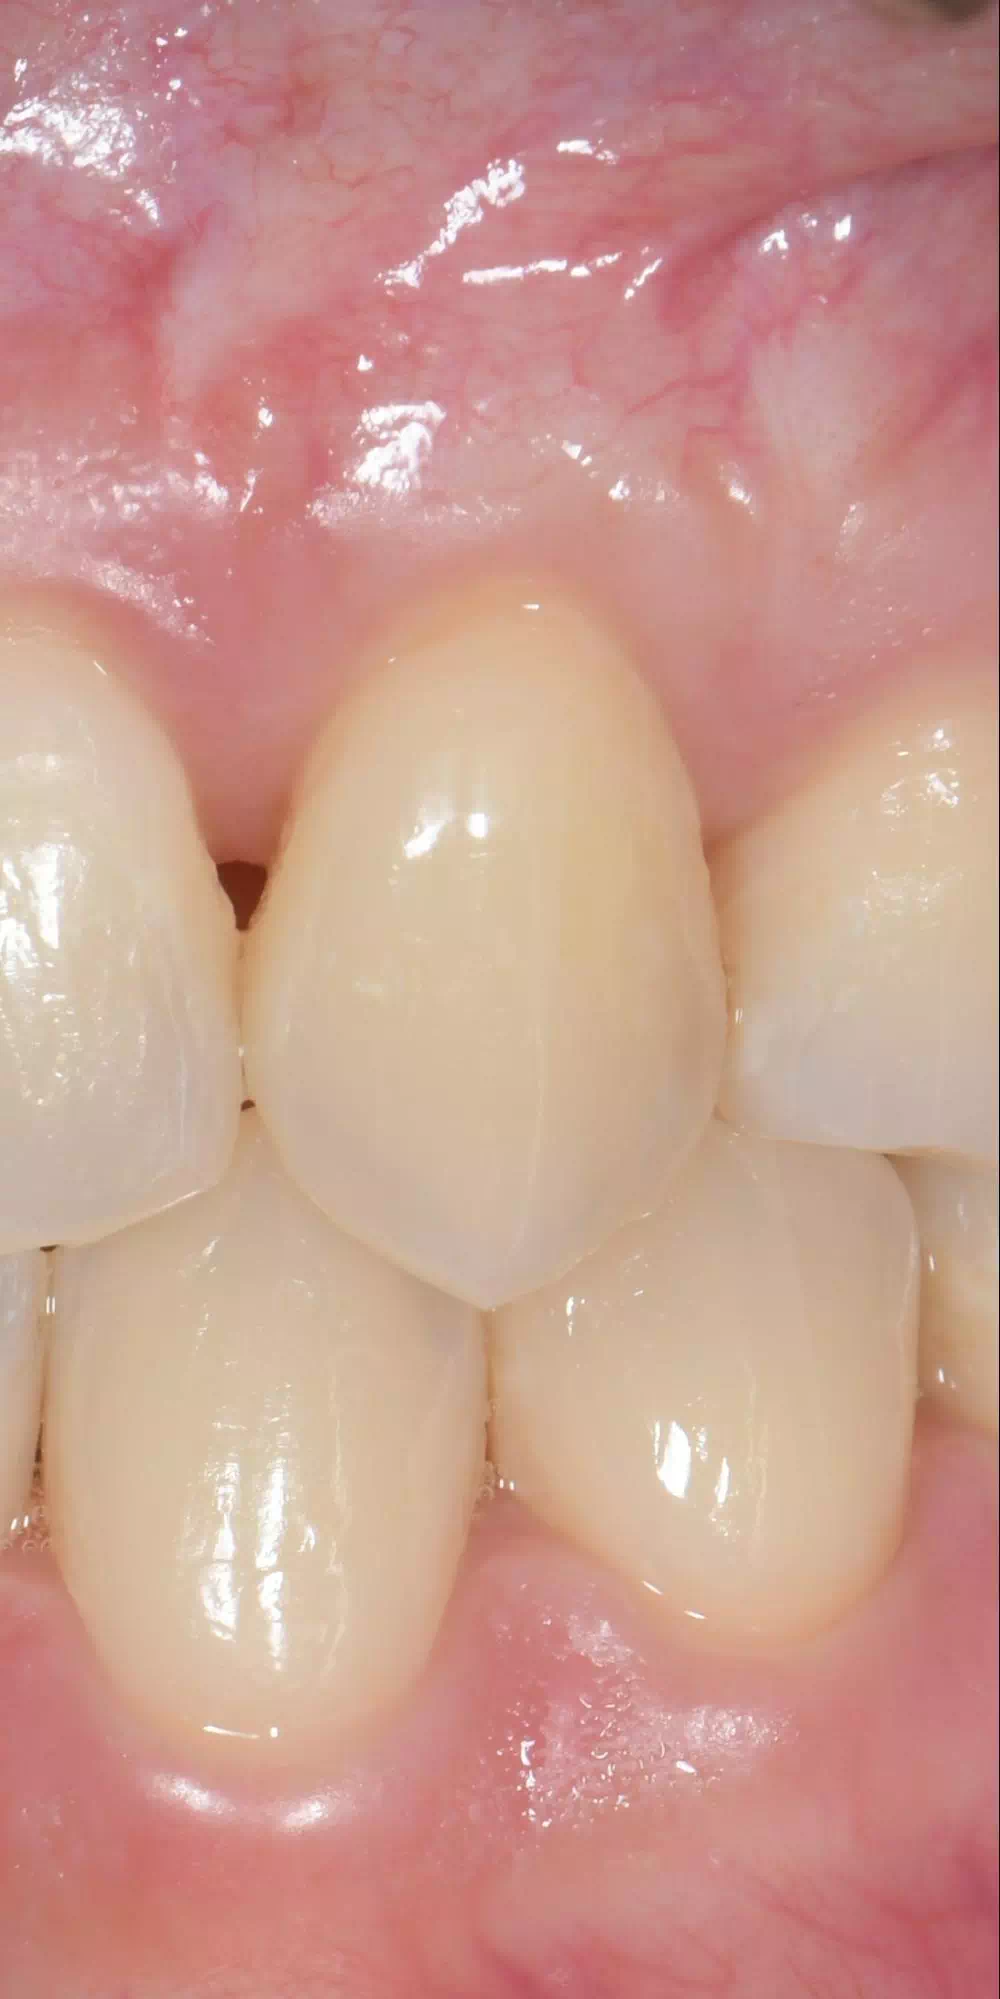

CASE HOME CASE 2025/10/21 抜歯即時埋入・即時荷重 症例 2025/10/21 GBR① 2025/10/21 インプラント 症例② 2025/10/21 インプラント 症例① 2025/10/21 矯正歯科 症例 2025/10/21 審美歯科 症例② 2025/10/21 審美歯科 症例① 2025/10/21 ガミースマイル 症例 2025/10/21 歯肉再生 症例② 2025/10/21 歯肉再生 症例① 2025/10/21 虫歯症例